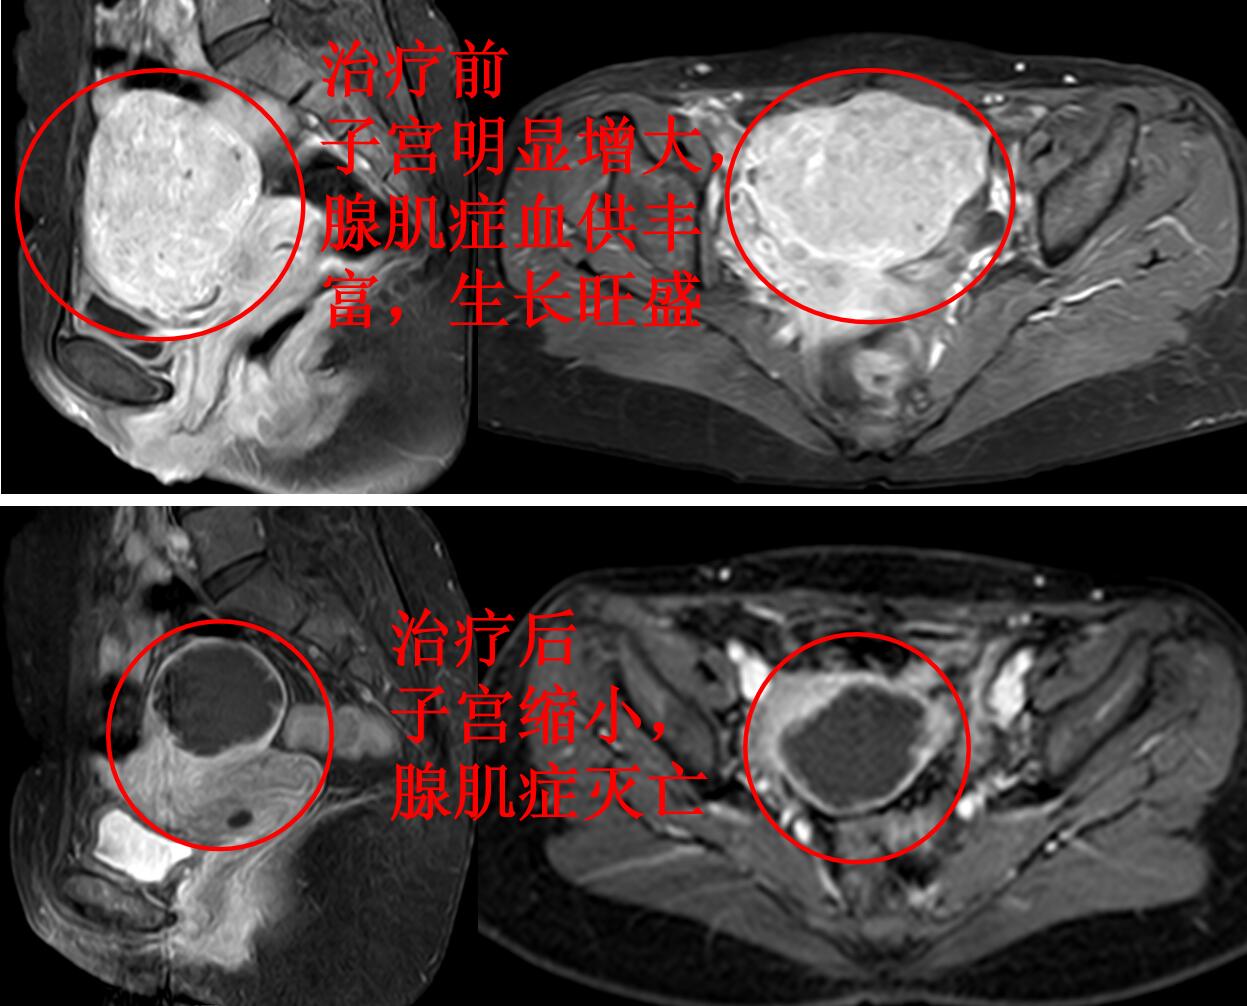

门诊磁共振检查:子宫明显增大(10.5*9.3*7.2cm3),子宫腺肌症,以左侧壁、宫底及后壁明显(如下图)。

下图为栓塞治疗前子宫腺肌症病灶的血供丰富,栓塞治疗后腺肌症血管堵塞,腺肌症灭亡。

介入微创栓塞治疗后无痛经,3个月复查的磁共振:子宫腺肌症完全灭亡,无血流,子宫缩小,治疗前后对比如下图。